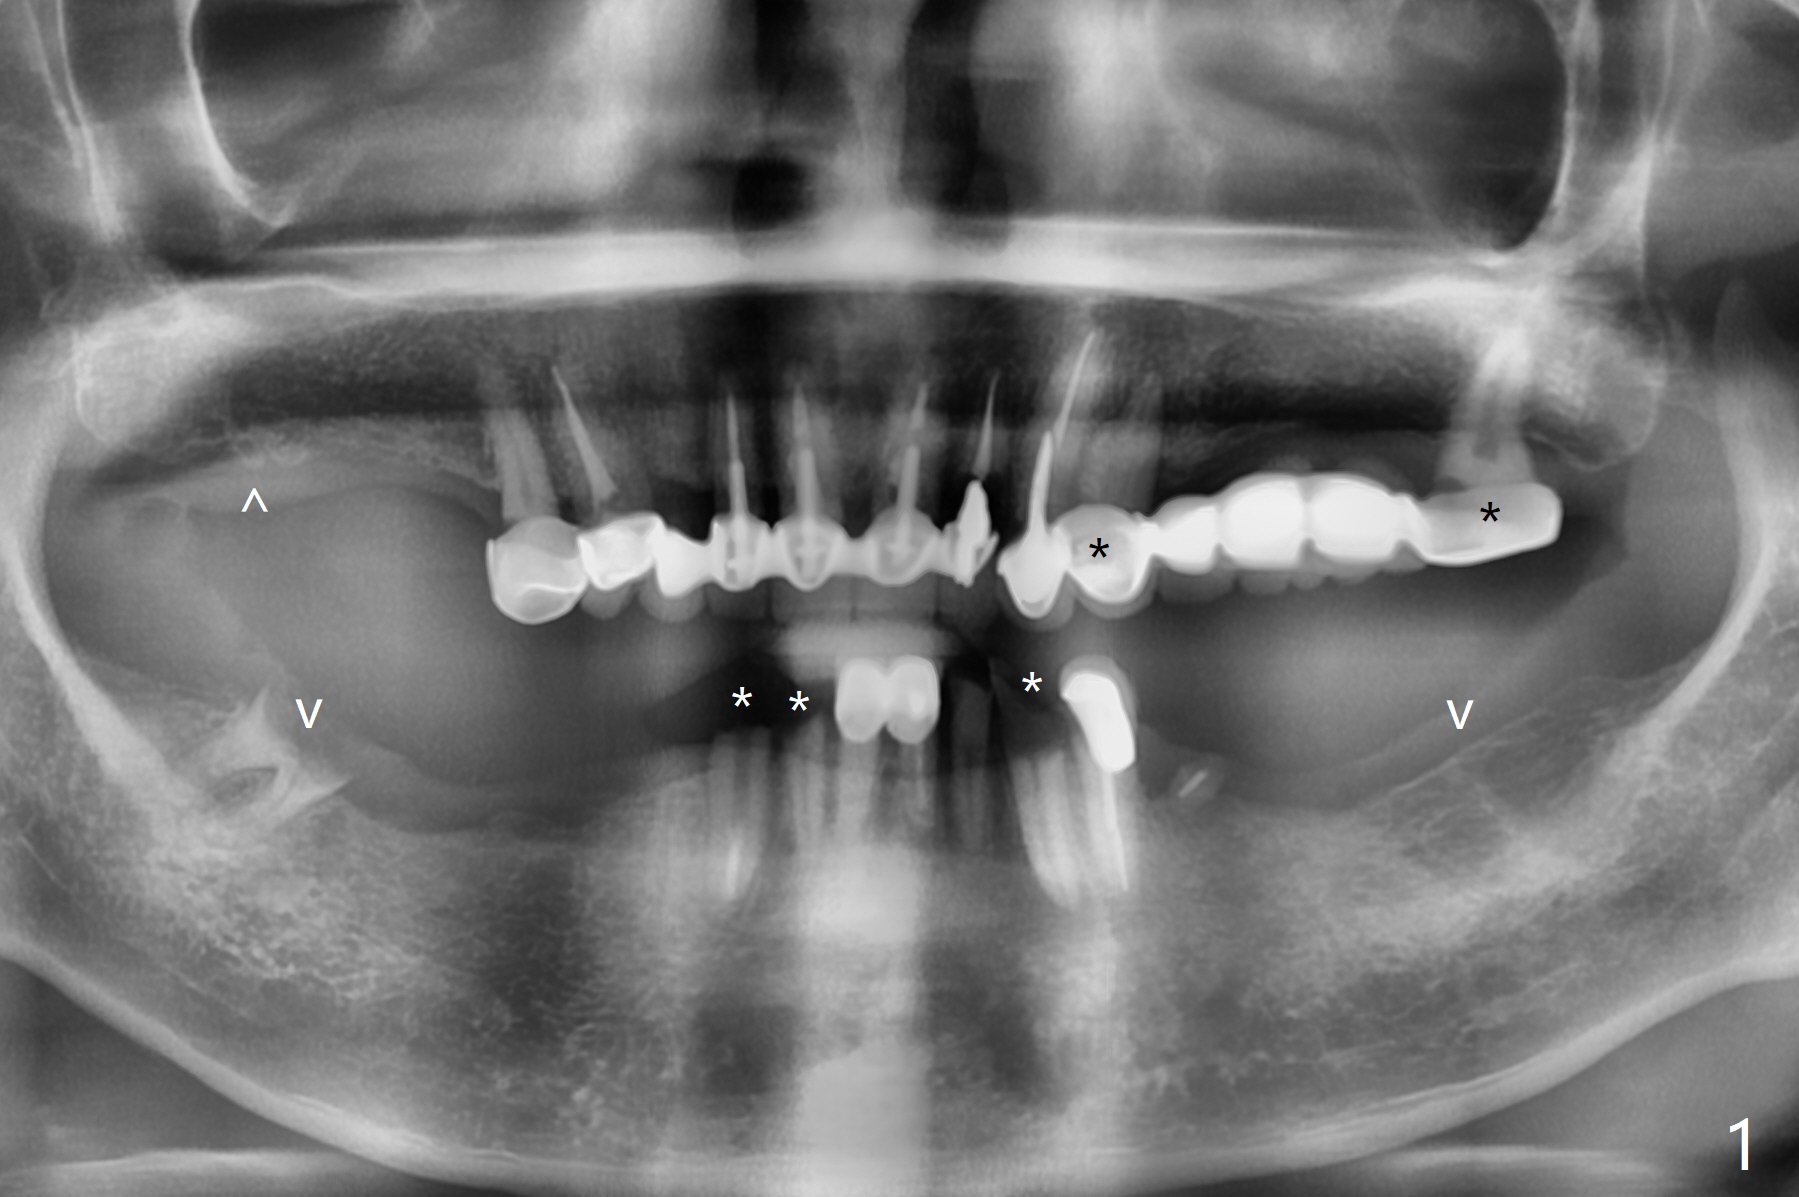

61男牙齿不好,左上4-8牙桥松动(图一,五,六),右下2,左下3根尖瘘道(图二),左上4,8也需要根管治疗,以上牙齿以及右下3插入球状牙桩(图一:*),然后在右上,左下,右下7植牙,放置球状基台(图一:箭头),固定上下活动义齿(覆盖义齿)。下前牙颊侧骨板几乎没有(图七)。左下7骨头(图八)宽于左下5(图三)。